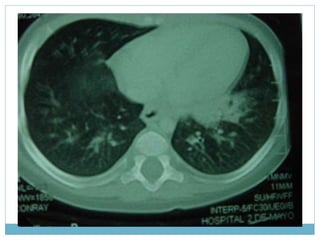

Rx de paciente de 2.5 años

Rx de pacientede 2.5 años